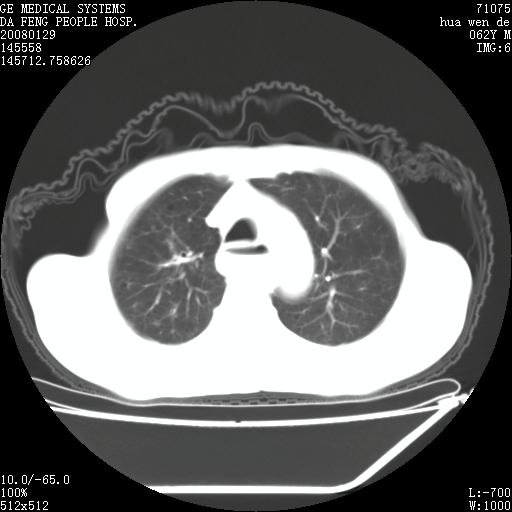

男性,67岁。作肺部检查时发现

理由:1、右上肺内病灶,空洞形成,有液平。

2、肺内多处炎症。

3、前段肺内炎症,支气管引流通畅,与肿块无关系。

1.整个食管扩张,未见明显占位性病变,贲门区亦未见明显占位病变,考虑:贲门失驰缓症;

2.右上肺病变边缘可见毛刺,囊壁厚度不均匀,周围境界较清楚,未见炎性渗出性影,右上肺外带可见片状影,边缘不清,考虑:肺癌伴空洞形成、右上肺炎。

食管全程扩张,壁均匀不厚,喷门失弛缓症

右上肺空洞可见液平,临近肺野磨玻璃密度,考虑1.结核2.脓肿